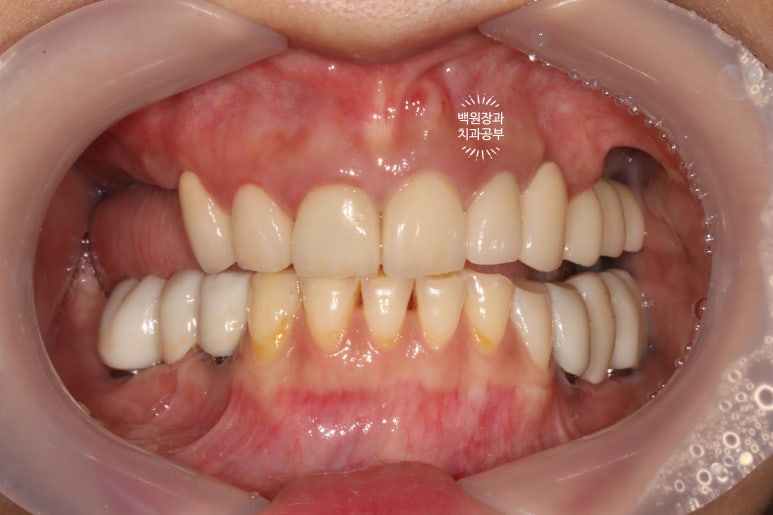

처음에 계획했던 5개의 어금니 임플란트와 3개짜리 지르코니아 브릿지 완성 후 정면 사진입니다.

아주 깔끔하게.... 정말 이상적으로 완성된 것을 보실 수 있습니다.

양 옆모습을 돌려서 보시면 위어금니와 아래어금니가 확연히 비교되는 것을 보실 수 있을겁니다.

일단 치아 경계 잇몸에 은색으로 보이는 부분 없이 깔끔하게 마무리가 되었습니다.

색상도 무조건 하얗지만은 않아서 개인적으로 더 자연스러워졌다고 봅니다.